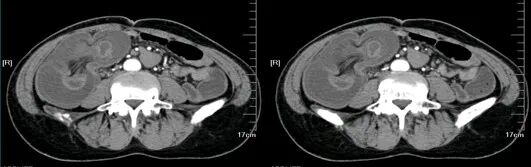

胰腺损伤

在交通意外中,尤其是汽车驾驶人员当汽车高速行驶中,汽车骤然撞于物体上,其强大的惯性使驾驶者的上腹部撞击于汽车方向盘上,导致胰腺受伤。有时当人体自高处坠落,腰部呈过度层曲,同时双侧肋弓极度内收,瞬间一个暴发力,挤压于胰腺上,造成胰腺不同程度的损伤。

胰腺损伤的部位,随外力的方向而异,以胰腺头、体部常见。当外力作用于右上腹或脊柱右侧方,则胰头部易被挤压,同时常合并有十二指肠、胆道、肝脏损伤,此类损伤后果严重,死亡率甚高可达70%~80%;当外力直接作用于上腹中部,则损伤多为胰颈、体部的部分或完全断裂,并合并有肠系膜上动脉损伤;外力作用于脊柱左侧方,胰尾常易受伤,此时多伴有脾破裂。